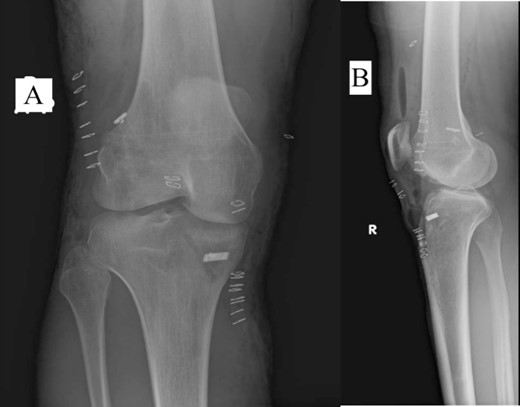

A 23-year-old male veterinarian presented to our out-patient department postright ACL reconstruction with hamstring autograft, PHMM tear by all-inside repair via sMCL pie-crusting technique, and lateral extra-articular tenodesis (modified Lemaire) in June 2023. A preoperative plain radiograph of the right knee revealed no evidence of HO (Fig. 1). No evidence of heterotopic ossification was detected in the right knee on plain radiographs taken 2 weeks postsurgery. (Fig. 2). Five months postsurgery, plain radiographs revealed new bone formation at the medial femoral condyle, precisely where the sMCL femoral origin was located (Fig. 3). The patient was asymptomatic and continued with rehabilitation. Seven months after the surgery, the patient started to complain of pain and clicking sensations when the right knee was flexed beyond an angle of 130°. Magnetic resonance imaging revealed consolidation of the newly formed bone, leading to a diagnosis of HO post-sMCL pie-crusting (Fig. 4). Nine months following surgery, the patient began to feel a bony mass on the medial side of the right knee. A plain radiograph and computed tomography (CT) scan revealed the complete formation of a bone island (Fig. 5). The past surgical history of this patient revealed that he had undergone left knee ACL reconstruction with hamstring autograft in December 2021, which failed and was complicated by a PHMM tear. The patient had presented to our facility for a revision. A revision ACL reconstruction was done using a bone-tendon-bone (BTB) autograft and PHMM tear all-inside repair via the sMCL pie-crusting technique in February 2022. A 2-year follow-up of the left knee, including physical examination and 3D-CT scans (Fig. 6), revealed no symptoms or signs of HO, although the same technique of sMCL pie-crusting was employed. Our patient suffered no head trauma during treatment. Past medical, drug, allergy, family, social histories, and reviews of systems were irrelevant to our case.

Plain radiograph of right knee AP (A) and lateral (B) 5 months postoperative showing initial HO.